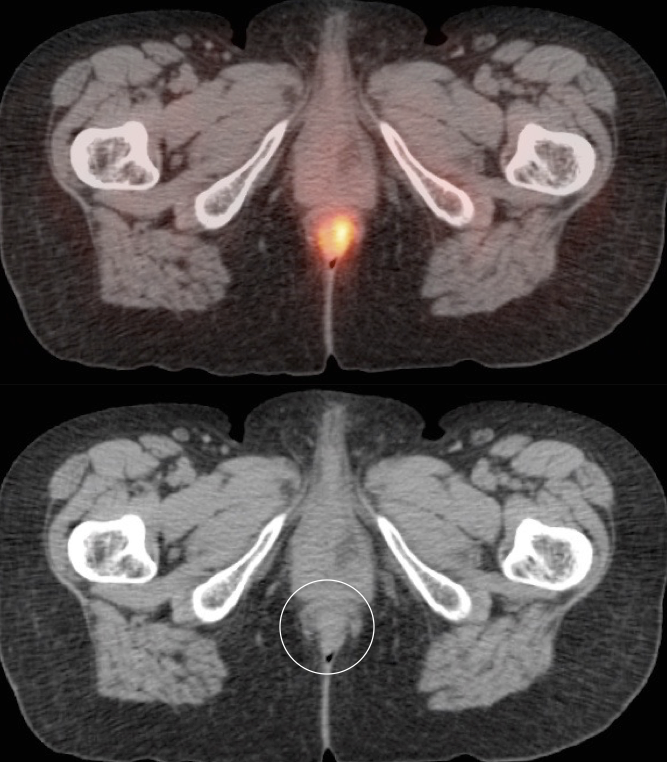

• Beware the small rectal cancer!  As the ano-rectal region frequently demonstrates intense physiologic uptake, it is very easy to overlook a rectal malignancy, especially if it is an incidental finding.  To avoid this error, always evaluate the rectum carefully on the sagittal whole body images.  It is shocking to see how readily apparent a rectal cancer can be on these images, yet so easily overlooked in the axial plane.